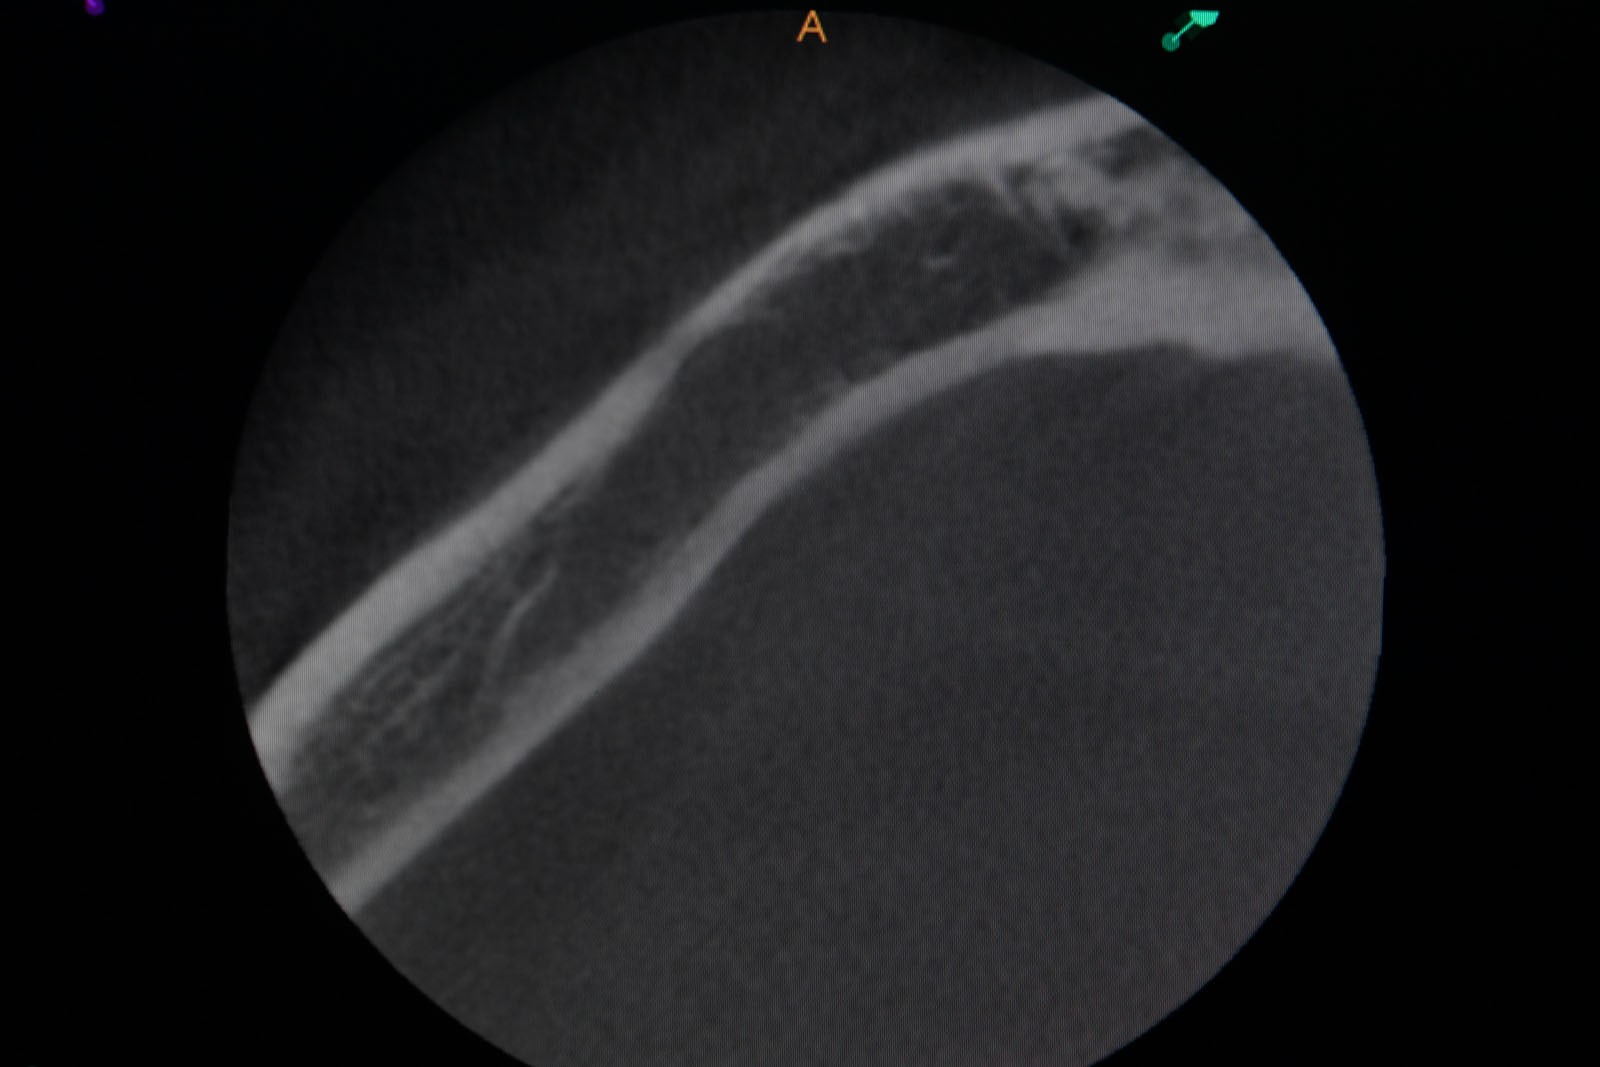

Przed podjęciem leczenia należy określić stopień zaniku kości szczęk oraz żuchwy. W tym celu przeprowadza się badanie kliniczne oraz odpowiednią diagnostykę obrazową pacjenta. Uwzględnia ona zdjęcie panoramiczne OPG jako podstawę dwuwymiarowego obrazowania podłoża kostnego oraz możliwe jest badanie tomograficzne CT lub bardziej precyzyjna tomografia stożkowa CBCT. Opcjonalnie wykorzystywana diagnostycznie tomografia pozwala na bardziej wnikliwą ocenę stopnia zaniku kości w trójwymiarowym, przestrzennym obrazie.

Zatoki szczękowe to symetrycznie umieszczone w kościach szczęk przestrzenie powietrzne, posiadające komunikację z jamą nosa. Średnio pojemność zatok wynosi 24 cm3, a ściany wyścielone są błoną śluzową (membrana Schneidera). Dno zatoki szczękowej stanowi wyrostek zębodołowy, w którym umieszczone są zęby, często zlokalizowane tuż pod cienką wyściółką zatoki. Statystycznie najwęższy obszar kostny w tej strefie zlokalizowany jest na wysokości zębodołów pierwszego i drugiego zęba trzonowego.